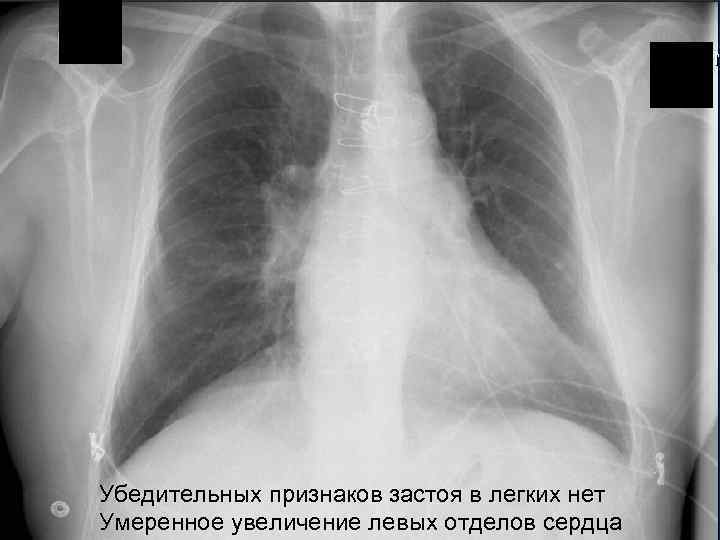

Пациент: мужчина, 70 лет Жалобы: - Острая одышка, ухудшается в течение 14 дней, Отмечает перебои в работе сердца Болей в грудной клетке, кашля не отмечает Анамнез: - ИБС+ ГБ, АКШ (2 года назад) - ТЭЛА (2 года назад) Объективно: - ЧДД в мин, АД 170/80 мм рт. ст. , ЧСС 90 в мин - Вены шеи не набухшие, хрипов нет, патологические шумы и тоны отсутствуют; отеки голени (больше слева) Принимает: диуретики, бета-блокаторы, аспирин, аторвастатин

Убедительных признаков застоя в легких нет Умеренное увеличение левых отделов сердца